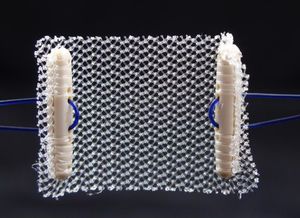

banda de reconstrucción para la incontinencia urinariaRemeex

... Sistema ajustable y re-ajustable a largo plazo para el tratamiento de todo tipo de incontinencia urinaria masculina de esfuerzo. El único sistema reajustable a largo plazo. El sistema Remeex Male es una mini malla ajustable y reajustable a largo ...